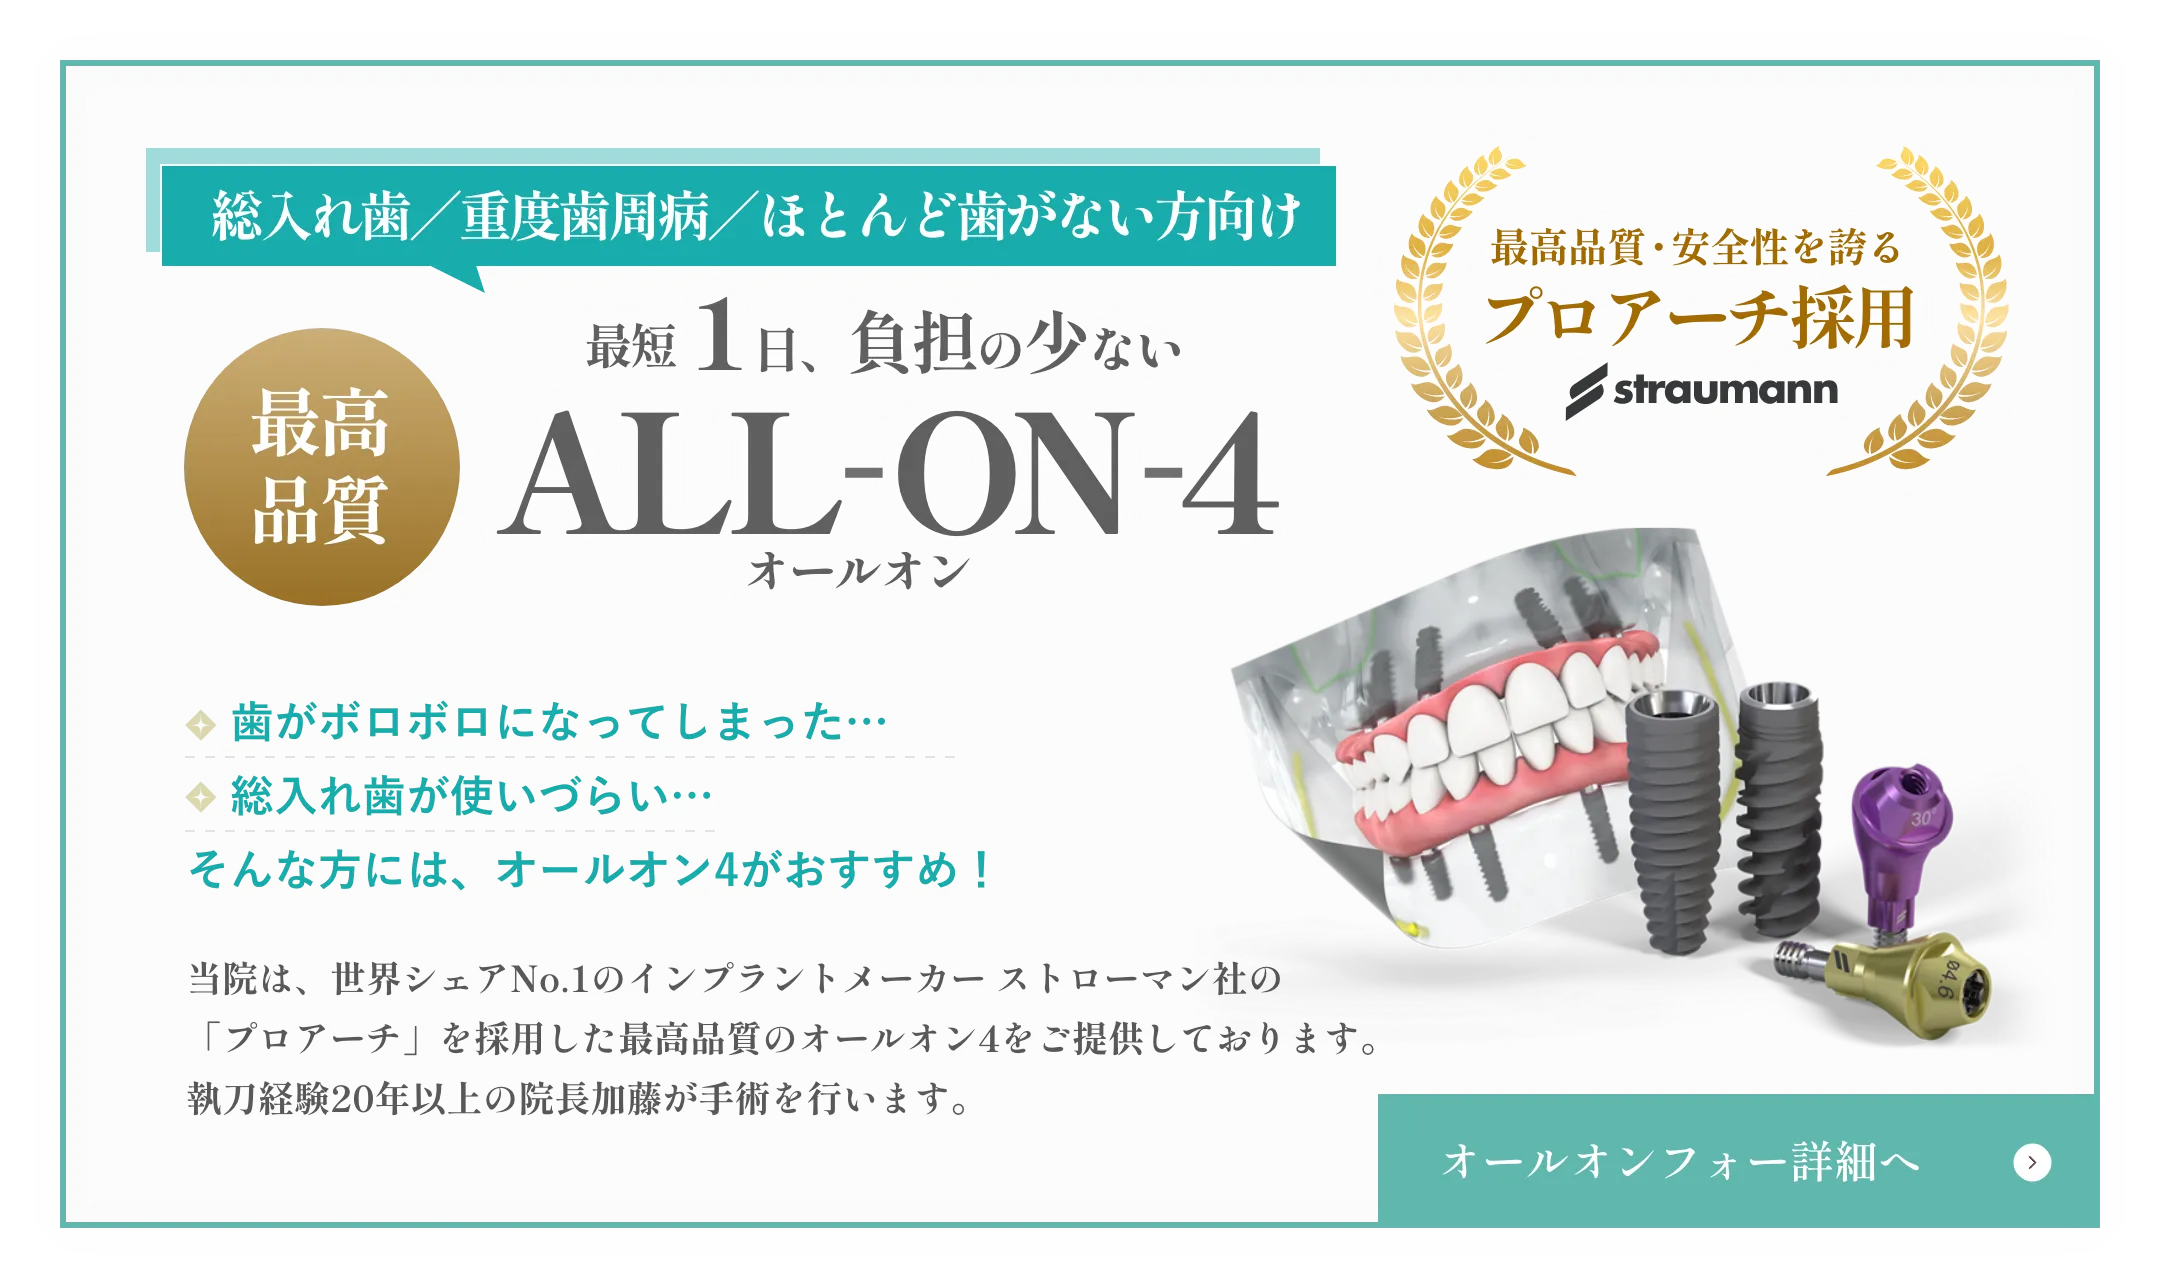

MEDICAL EQUIPMENT

CTスキャンを活用し、

患者様の口腔内を

3Dデータで精密に解析

加藤総合歯科・矯正歯科では、CTスキャンにより口腔内を3D化し、

コンピューターシステム「ビオナ」で歯の状態を詳しく解析します。

専門医とコンピュータ技術が連携し、インプラントの位置や角度をミリ単位で正確に決定、手術時のリスクを最小限に抑えます。

精密な手術計画と

シミュレーションを通じて、

治療の負担を最小限に抑えます。

インプラント治療では、患者様の体にかかる負担を軽減するため、入念な治療計画を立ててから実施します。治療計画患者様に十分に説明し、ご理解とご納得を得た上でい進めていきます

さらに、インプラント埋入位置を正確に決定するため、サージカルガイドを使用し、歯ぐきをほとんど切開せずに手術を行うことで、術後の腫れや痛みを最小限に抑えます。

サージカルガイドで

インプラント位置の精度を向上

経験豊富な院長による

慎重な手術

当院の手術は

ミリ単位の精度で行います